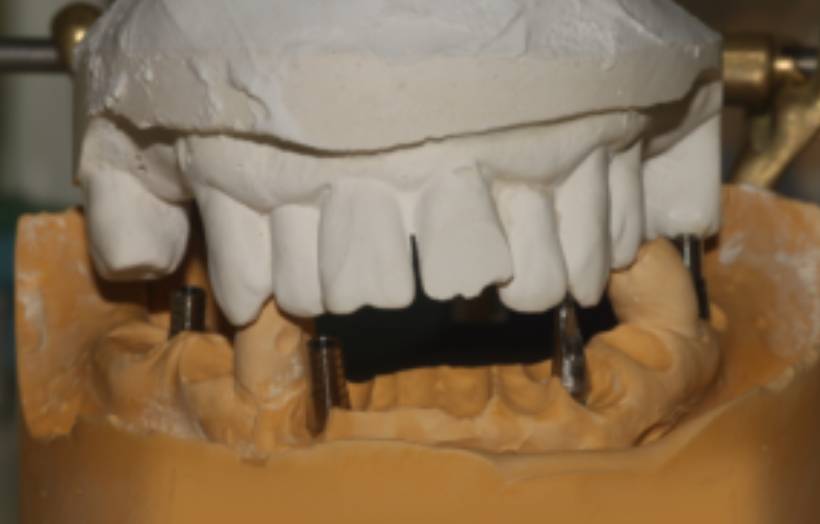

Dental Rehabilitation Using Alpha Dent Implant in Case of Reconstructed Mandible after Excision of Ossifying Fibroma

Dental Rehabilitation Using Alpha Dent Implant in Case of Reconstructed Mandible after Excision of Ossifying Fibroma Dr. Parit Ladani MDS